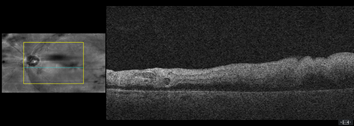

Dilated fundus examination revealed relatively normal fundus with cup-to-disc (C/D) ratio of 0.30 round OD (Figure 1A). The fundus photo of the left eye showed a pale posterior pole with swollen optic nerve head and macular cherry spot (Figure 1B). Ocular coherent tomography (OCT) macular cube scans showed a representative slice of normal retinal layers through the macula OD (Figure 2A), and a pigmented epithelial detachment and disrupted retinal layers extending temporally from the optic nerve head (ONH) OS (Figure 2B). Additionally, Figure 3 and Figure 4 showed the OCT optic disc cube 200x200 scan with swollen ONH OS, and OCT macular cube 512x128 scan with detached retinal layers OS, respectively.

Figure 2B a slice of OCT macular cube showing pigmented epithelial detachment, and disrupted retinal layers OS.

This case report is rare because the patient suffered both from an acute CRAO and PED after a prolonged coughing episode. His ONH was swollen with indistinct margin, and the posterior pole was pale with a typical fovea cherry spot (Figure 1B). Extensive swelling of inner retina and PED extending from the ONH were apparent on OCT imaging (Figure 2B). When he showed up to the UCC the next day, it had already passed the critical window of 6 hours so not much could be done ocularly to reverse the retinal damages in the left eye. The patient was referred to a local retinal specialist who then sent the patient to the emergency department for a more extensive stroke work up at a local hospital emergency department. There, he was found to have left proximal ICA stenosis, chronic atrial fibrillation, interstitial lung disease, chronic GERD, and severe shoulder arthritis. Then, he was discharged in stable condition and scheduled to have continued care with retinal specialist, PCP, pulmonologist and cardiologist.